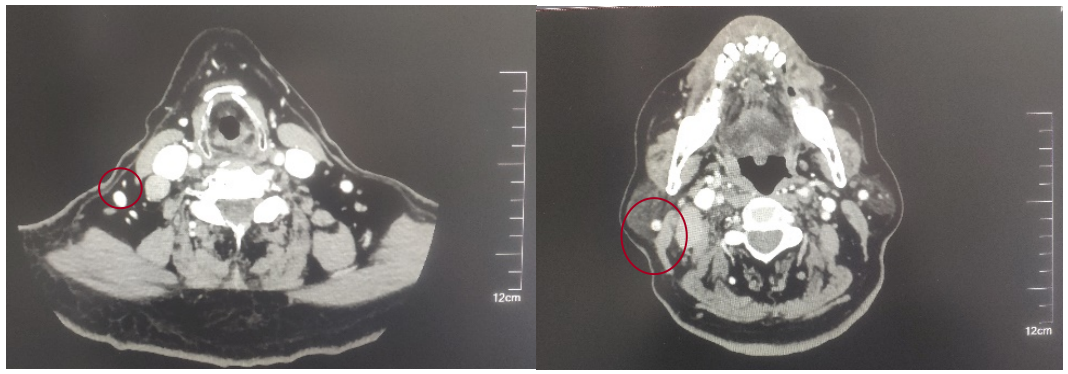

2022-05-05鼻咽部增强CT示:鼻咽CA并左侧翼腭弓、海绵窦受侵,伴邻近蝶窦、左侧筛窦、枕骨斜坡、左侧框下裂骨质破坏;右侧颈部多发肿大淋巴结(最大2.4×1.4cm),考虑转移;2.双侧梨状窝闭塞。

2022-05-09行“斯鲁利单抗300mg d1+紫杉醇脂质体150mg d1,120mg d8+奈达铂150mg d2+尼妥珠单抗400mg d2”治疗1周期。

后患者至江苏省肿瘤医院放疗科就诊,2022-06-06完善头颅MR检查: